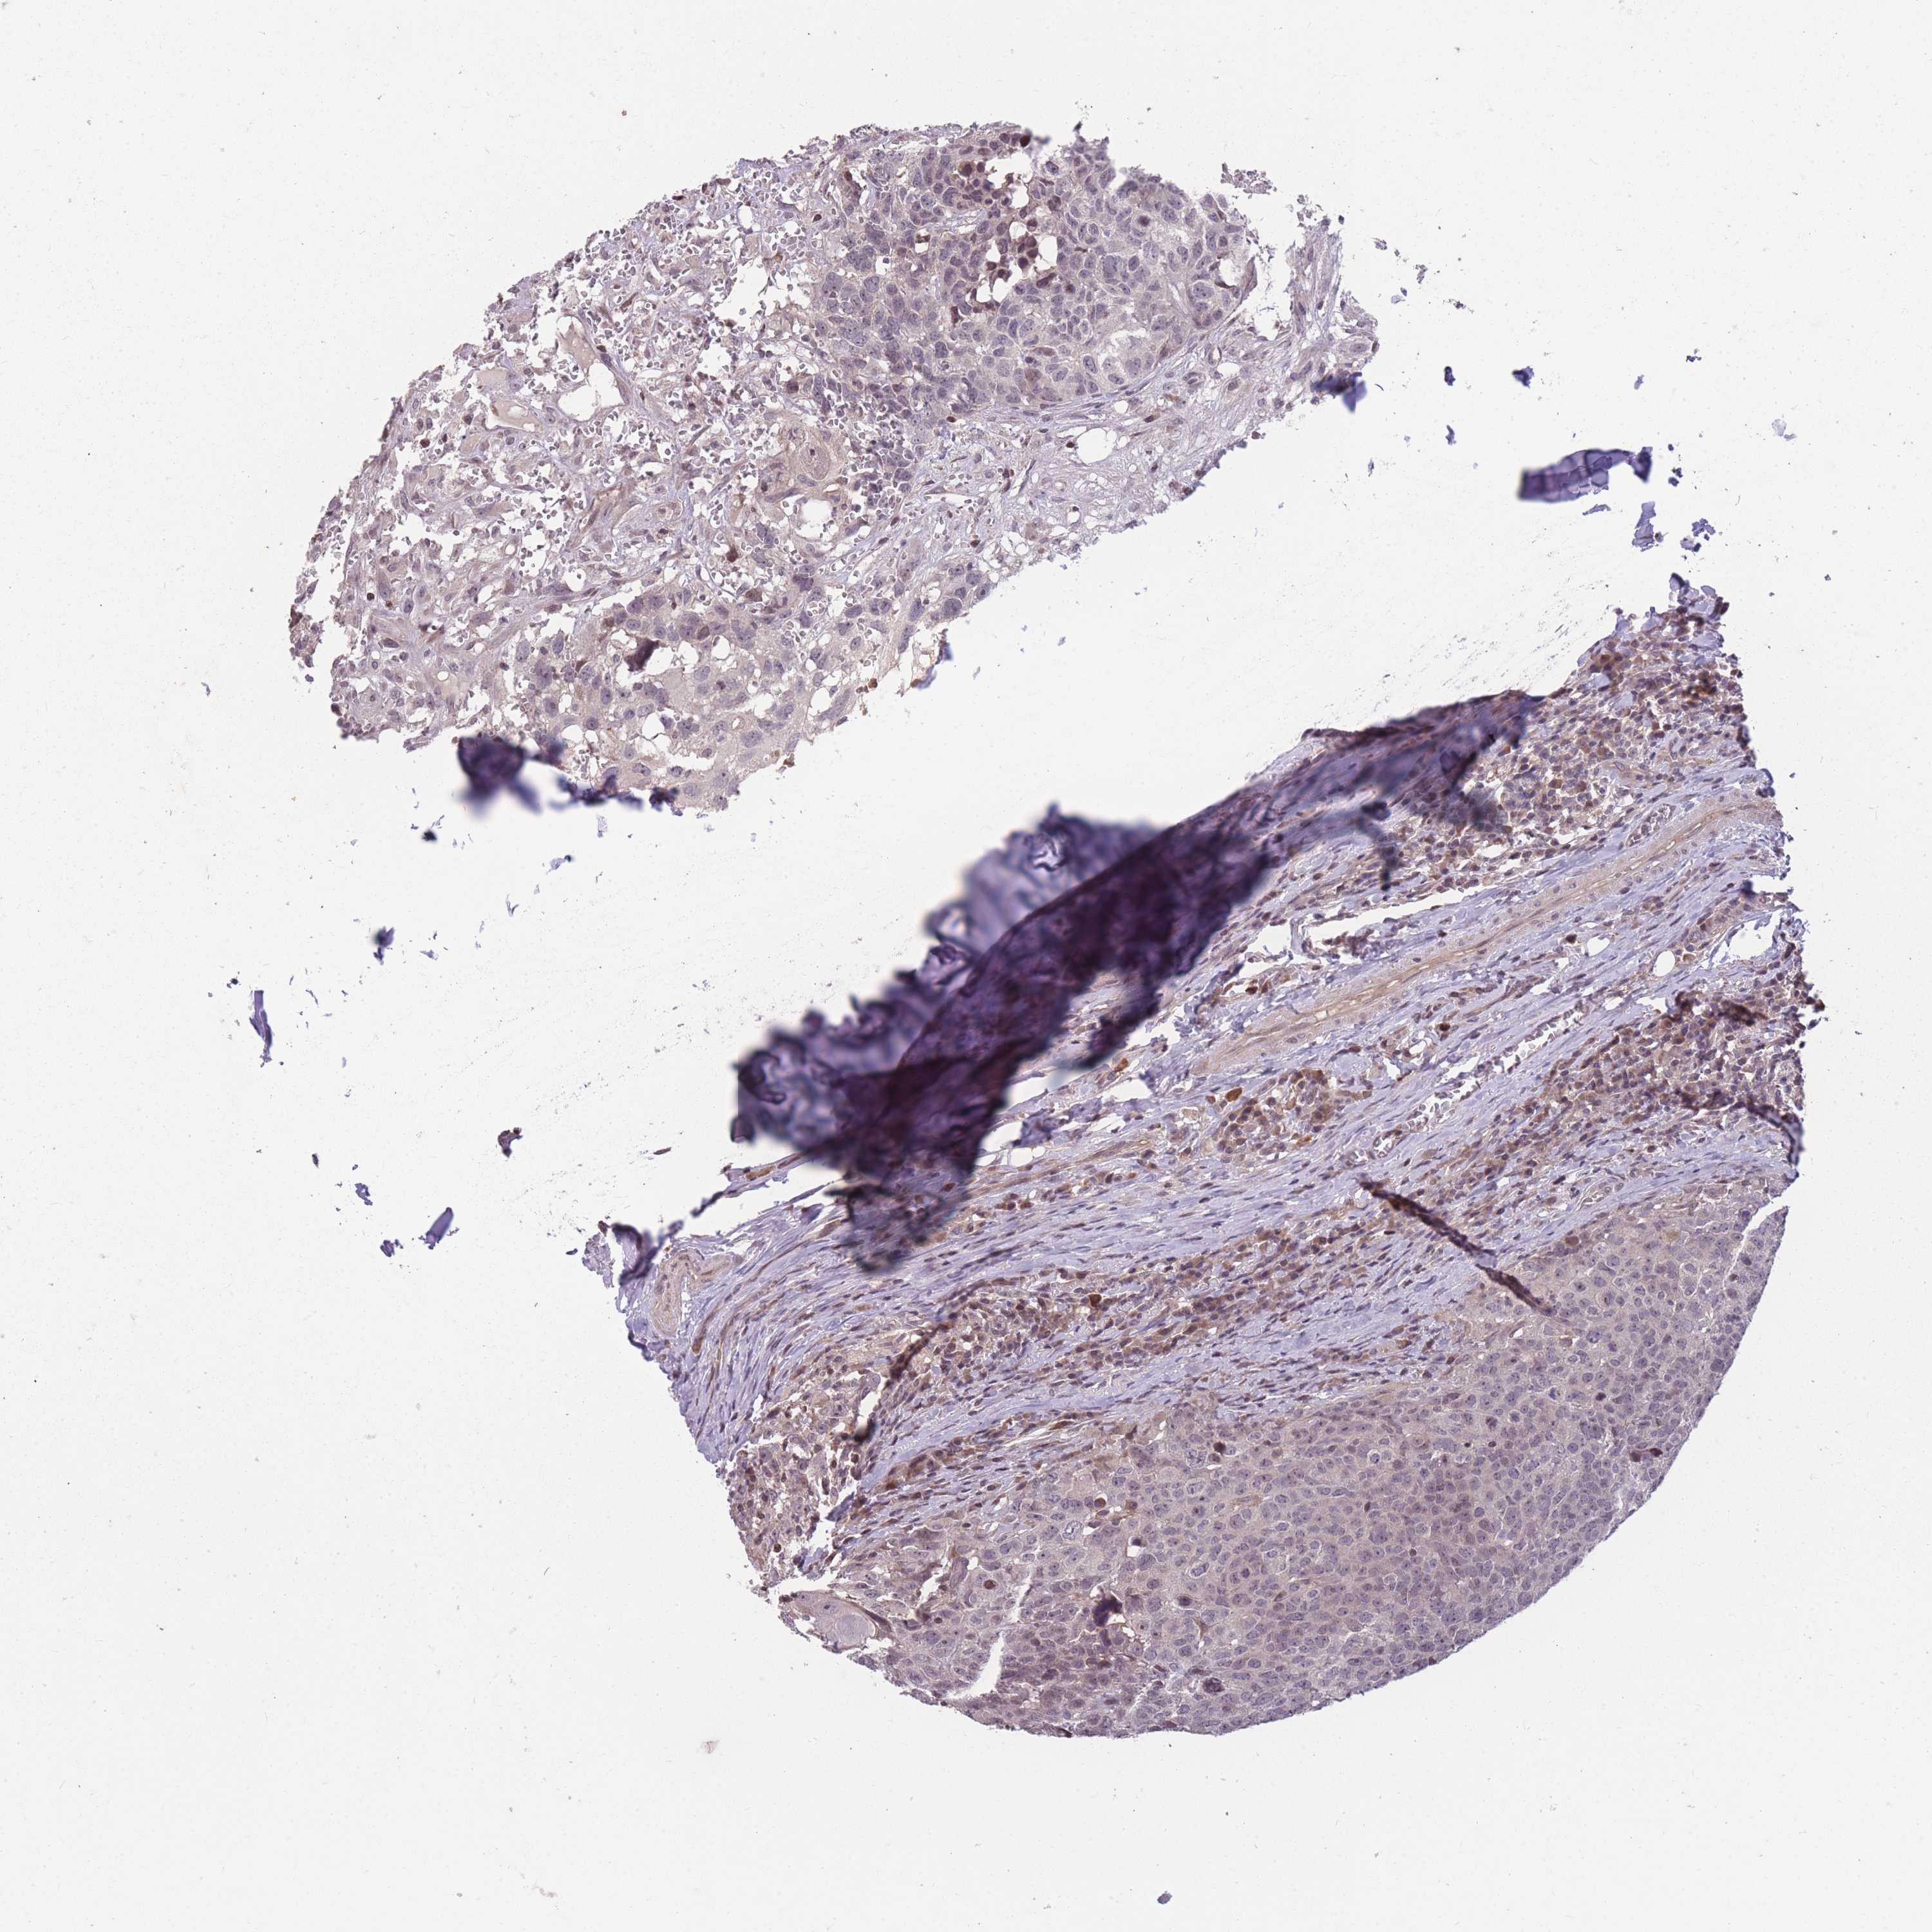

HEAD AND NECK CANCER - Protein expressioni

A mouse-over function shows sample information and annotation data. Click on an image to view it in a full screen mode. Samples can be filtered based on level of antibody staining by selecting one or several of the following categories: high, medium, low and not detected. The assay and annotation is described here.

Antibody stainingi

Antibody staining in the annotated cell types in the current human tissue is reported as not detected, low, medium, or high, based on conventional immunohistochemistry profiling in selected tissues. This score is based on the combination of the staining intensity and fraction of stained cells.

Each image is clickable and will lead to virtual microscopy that enables deeper exploration of all samples and also displays staining intensity scores, fraction scores and subcellular localization as well as patient and tissue information for each sample.

Antibody HPA008121

Antibody CAB032489

Staining

High

Medium

Low

Not detected

Intensity

Strong

Moderate

Weak

Negative

Quantity

>75%

75%-25%

<25%

None

Location

Nuclear

Cytoplasmic/membranous

Cytoplasmic/membranous,nuclear

Squamous cell carcinoma, NOS

Adenocarcinoma, NOS